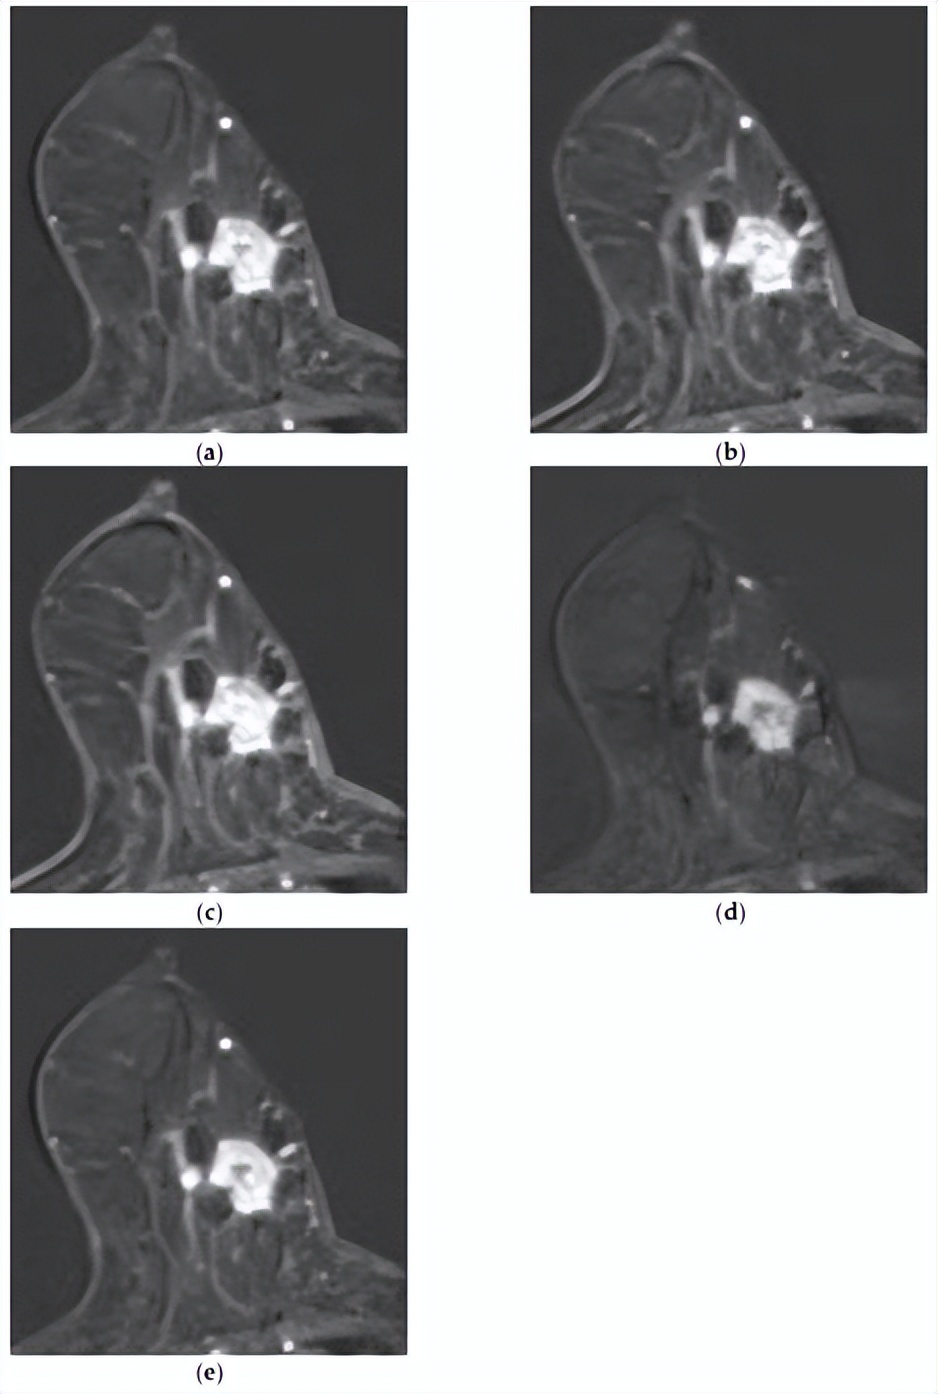

[组合模型正确预测了复发,而MRI模型则没有。一名73岁的女性,乳房几乎完全脂肪化,BPE极小。注射造影剂后(a)1分钟、(b)2分钟、(c)3分钟、(d)4分钟和(e)5分钟的轴向增强T1加权MR图像显示,右下内象限有一个1.4×1.7厘米的不规则形状、边缘不规则肿块,内部增强不均匀。病灶表现出快速的初始增强,随后呈现平台期动力学曲线模式。未发现腋窝淋巴结转移。MRI深度学习模型无法预测该复发病例,但整合临床病理学和MRI特征的组合模型可以正确预测。]